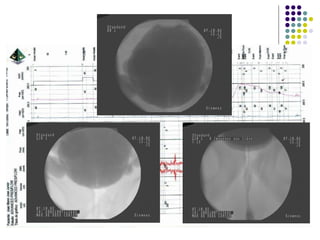

Exames de imagem, endoscopia. Trato urinário  superior Trato urinário Inferior

Urodinâmica. Avaliação urodinâmica é a reprodução dos sintomas  do paciente sob condições controladas. Caracterização da função do detrusor e da função esfincteriana. Indicação formal na suspeita de disfunção neurológica

Cistometria. Avaliação componente passivo durante o enchimento. Valor limitado como   procedimento isolado. Estudos miccionais. Vídeo.

Exames de imagem,endoscopia. Trato urinário superior Trato urinário Inferior

Urodinâmica. Avaliação urodinâmicaé a reprodução dos sintomas do paciente sob condições controladas. Caracterização da função do detrusor e da função esfincteriana. Indicação formal na suspeita de disfunção neurológica

Cistometria. Avaliação componentepassivo durante o enchimento. Valor limitado como procedimento isolado. Estudos miccionais. Vídeo.

• #13 A avaliação urodinâmica engloba medidas de extrema simplicidade como o registro de diários miccionais até complexas avaliações monitorizadas por microcomputadores ligados a periféricos que convertem as variações de pressão em dados. O estudo pode ser acompanhado através de imagens obtidas por intensificadores de imagem e/ou ecografia, permitindo uma avaliação visual da pelve e trato urinário inferior.